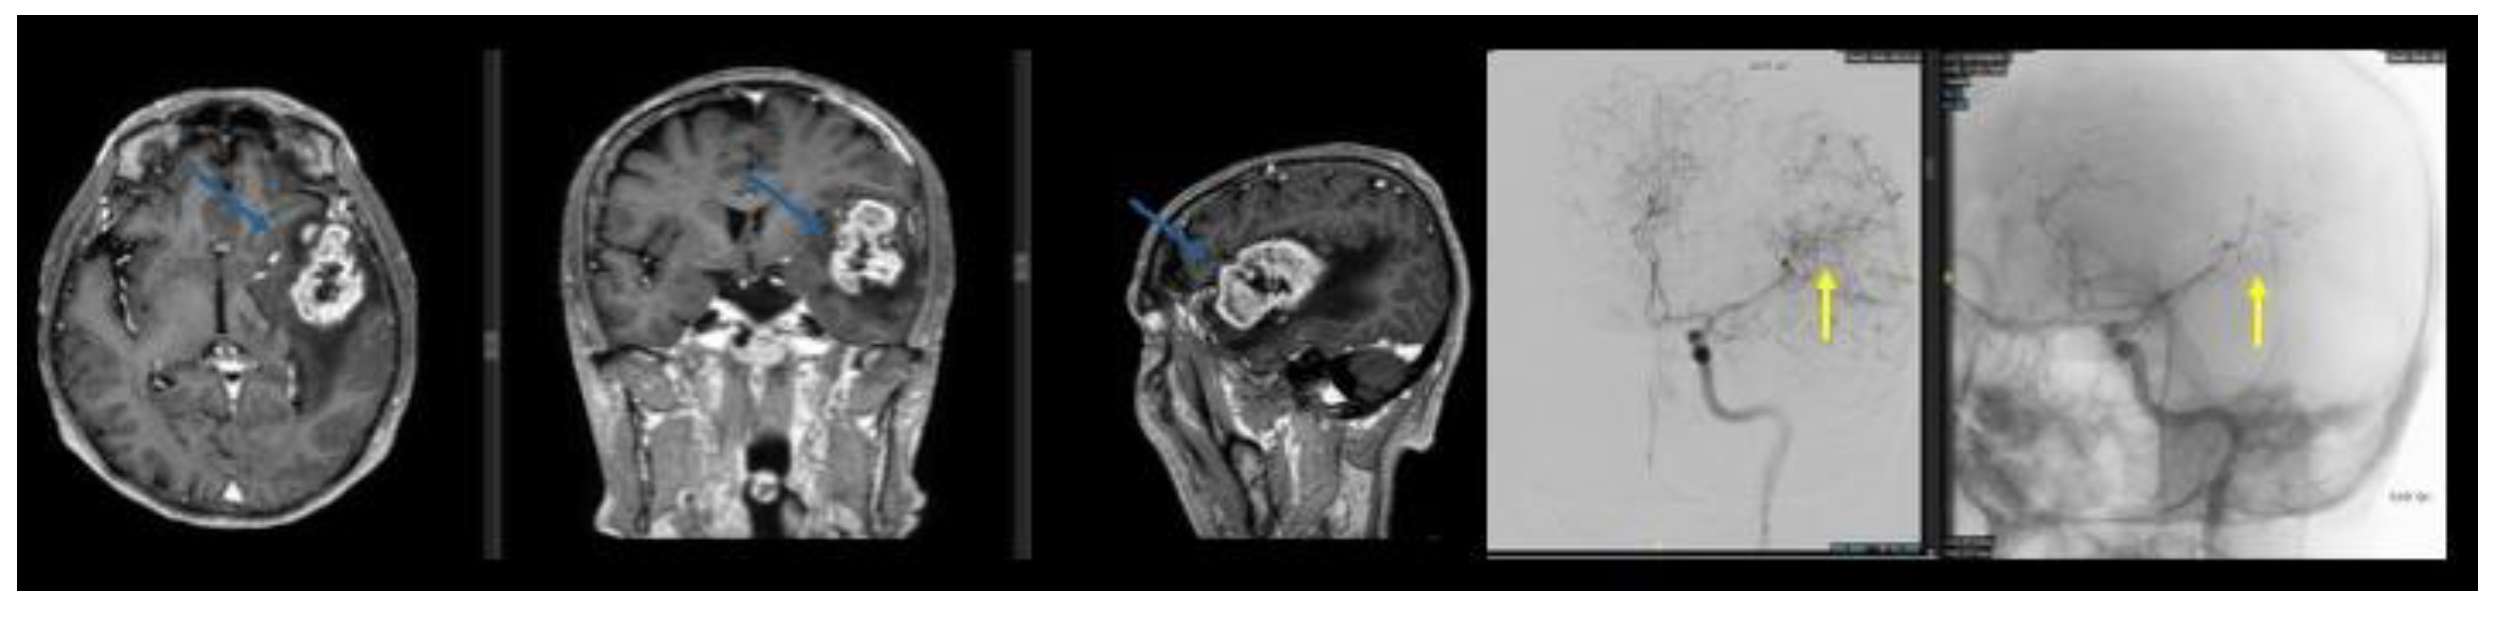

Background and Clinical Significance: Glioblastoma is the most common and aggressive primary malignant brain tumour in adults. Maximal safe surgical resection remains the cornerstone of treatment; however, tumour vascularisation may increase the risk of in-traoperative bleeding and complicate surgical management. Preoperative endovascular embolisation is commonly used for highly vascular intracranial tumours such as men-ingiomas, whereas its role in glioblastoma remains poorly defined. A focused literature review using the search string (((preoperative) AND (endovascular)) AND (embolization)) AND (glioblastoma) identified only two relevant publications, highlighting the scarcity of available evidence. In this context, we report a case series of three patients with intra-cranial lesions suspected to be high-grade gliomas who underwent preoperative angi-ographic evaluation and, when feasible, endovascular embolisation prior to surgical resection. Case Presentation: Three patients presenting with large intracranial lesions suggestive of high-grade glioma underwent preoperative digital subtraction angi-ography to assess tumour vascular supply (histological analysis confirmed the diagnosis of glioblastoma). In a 61-years-old woman with a right frontal tumour, selective catheteri-sation of a frontal branch of the right anterior cerebral artery enabled embolisation with coils, achieving partial tumour devascularisation before surgery. A second patient, a 53-year-old man with a large left temporo-fronto-insular mass extending to the corpus callosum, underwent embolisation of tumour feeders arising from the anterior choroidal artery using N-butyl cyanoacrylate and Lipiodol prior to resection. In a third case, a 77-year-old man with a left temporo-parietal lesion underwent preoperative angiography that demonstrated tumour capillary blush but no catheterisable feeding arteries, and embolisation was therefore not feasible. All patients subsequently underwent surgical resection without perioperative complications or new neurological deficits. Conclusions: Preoperative angiographic evaluation may help characterise tumour vascular supply in selected glioblastoma cases. When identifiable arterial feeders are present, endovascular embolisation may represent a feasible adjunct to facilitate surgical management. Further studies are required to better define the indications, safety profile, and potential benefits of this approach.